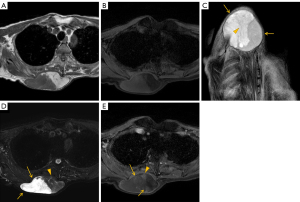

Representative MRI images are shown in Figures 1-3. Corresponding histopathological findings of the lesions in Figures 1,3 are shown in Figures 4,5, respectively.

In cases of fat-containing tumors, the T1WI signal intensity reflects fat content, which is diagnostically significant. Earlier studies have categorized ASPLT T1WI signal intensity into the following three groups: (I) high; (II) mixed high and low; and (III) low (6). However, since some high T1WI signals may be attributed to hemorrhage or myxoid components (8), this study focused on evaluating fat content using selective fat suppression techniques instead of T1WI signal intensity. Fat content varied widely, with an average score of 1.74 and median score of 1, indicating a tendency toward low fat content in the cases assessed. Histopathological examination similarly confirmed a tendency toward low fat content, with findings consistent with imaging in many cases (Figures 4A,5A). Furthermore, fat was not only interspersed within the nonfatty components but also often present as distinct nodules, which corresponded well with the MRI findings.

Regarding nonfatty components, T2WI high-signal areas appeared in 18 cases (94.7%), with 17 cases (89.5%) showing high-signal areas covering approximately 25% of the lesion. T2WI low-signal septa were observed in all cases. Contrast enhancement appeared in 15 of 16 cases (93.8%), predominantly in T2WI high-signal areas and in T2WI low-signal areas in 12 cases (75.0%). Histologically, abundant collagen fibers and myxoid material were observed in these lesions (Figures 4C-4E,5C-5E), which corresponded well with the signal characteristics on T2WI. Specifically, T2WI low-signal areas were considered to reflect collagen fibers, whereas high-signal areas were attributed to myxoid components. However, no discernible histological differences were observed that could account for the variation in contrast enhancement (i.e., moderate in Figure 4 and faint in Figure 5).

Other findings included well-defined margins in eight cases (42.1%) and capsular structures in 17 cases (89.5%). Margins have been reported to be indistinct owing to peripheral infiltration (2,4). In our pathological analysis as well, capsule-like structures were observed at the tumor margins; however, tumor infiltration beyond these structures was also identified in some areas (Figures 4B,5B). This suggests that the capsules observed on MRI may not represent true tumor capsules, but rather so-called “pseudocapsules” formed by compression or reactive changes in the surrounding tissue.

Edema-like signals appeared in two cases (10.5%) (positive, Figure 1; negative, Figure 3). However, corresponding tumor infiltration was not observed histologically (Figure 4C), suggesting that these findings were unlikely to affect surgical handling or postoperative outcomes.